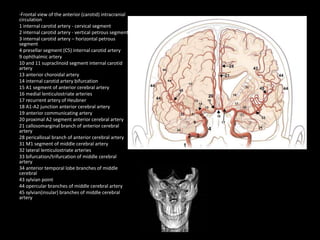

-Frontal view of the anterior (carotid) intracranial

circulation

1 internal carotid artery - cervical segment

2 internal carotid artery - vertical petrous segment

3 internal carotid artery – horizontal petrous

segment

4 presellar segment (C5) internal carotid artery

9 ophthalmic artery

10 and 11 supraclinoid segment internal carotid

artery

13 anterior choroidal artery

14 internal carotid artery bifurcation

15 A1 segment of anterior cerebral artery

16 medial lenticulostriate arteries

17 recurrent artery of Heubner

18 A1-A2 junction anterior cerebral artery

19 anterior communicating artery

20 proximal A2 segment anterior cerebral artery

21 callosomarginal branch of anterior cerebral

28 pericallosal branch of anterior cerebral artery

31 M1 segment of middle cerebral artery

32 lateral lenticulostriate arteries

33 bifurcation/trifurcation of middle cerebral

34 anterior temporal lobe branches of middle

cerebral

43 sylvian point

44 opercular branches of middle cerebral artery

45 sylvian(insular) branches of middle cerebral